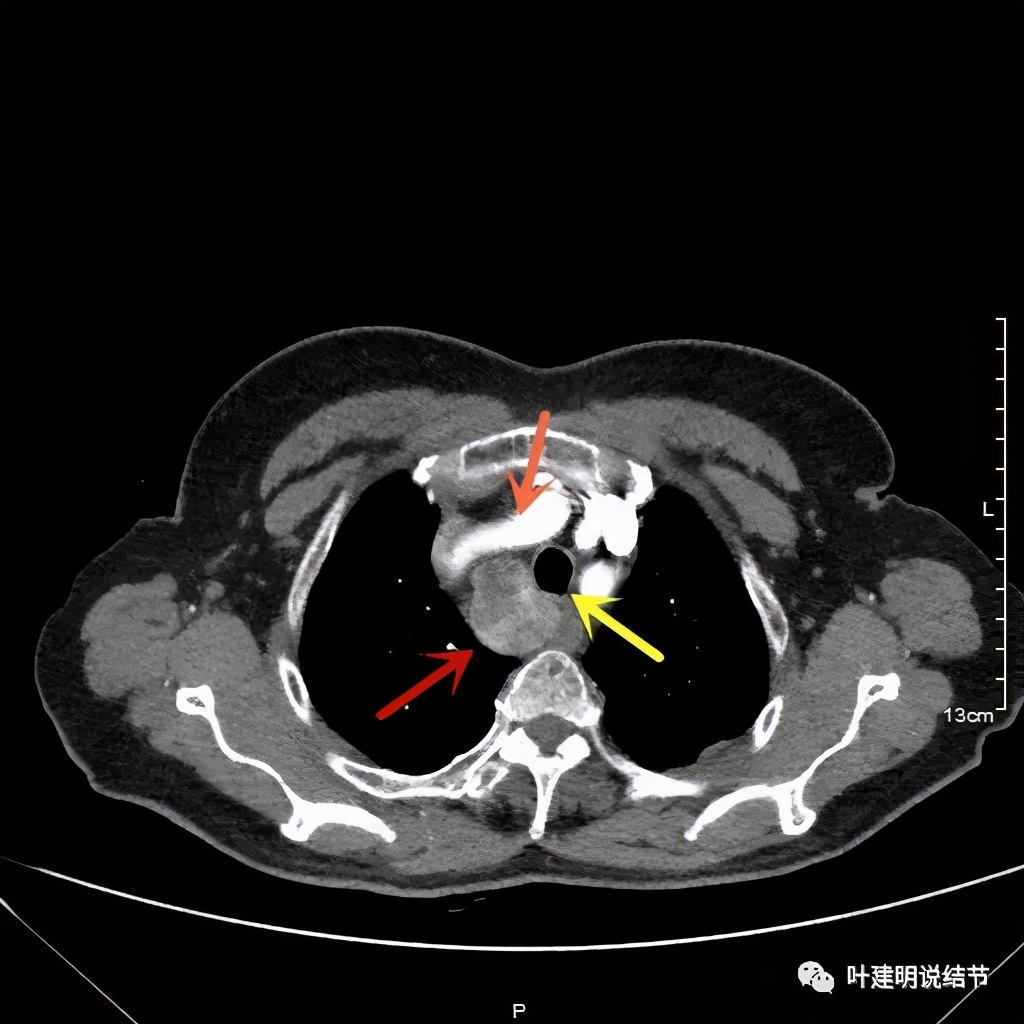

上图红色示肿瘤,黄色示气管,蓝色示上腔静脉

上图红色示肿瘤,黄色示气管,蓝色示上腔静脉,肿瘤已经快要消失了的层面,它距离隆突只有2点几厘米了,位置很低